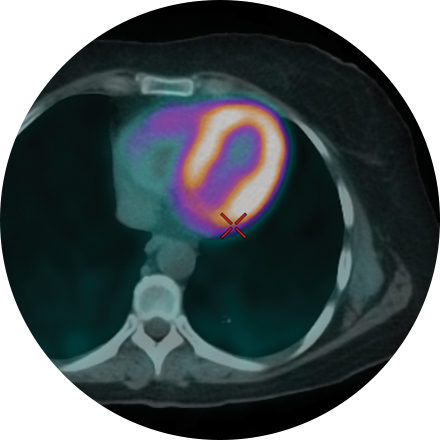

PET/CT combines Positron Emission Tomography (PET) with Computed Tomography (CT) technology to aid in the diagnosis of cancer, determining the extent to which cancer has spread, and assessing how a patient is responding to treatment. In addition, PET can be used to evaluate patients with cardiac and neurological disorders, such as seizures and dementia.

PET/CT is a nuclear medicine test that uses special imaging cameras and a radioactive solution called FDG (Flurodeoxyglucose) to create very clear pictures of a cell’s metabolism and if it is abnormal. CT uses X-rays to provide detailed anatomical information, including the location, size and shape of lesions or tumors in the body. When both applications are combined together, the two techniques provide accurate and specific information about where abnormalities are located and whether they are cancerous.